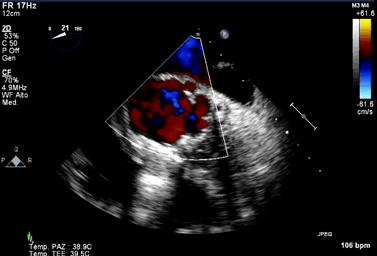

La TAVI “valve in valve”.

Categoria: Relazioni storiche Parole chiave: Area Cardio-Interventistica complicazione malfunzionamento mismatch protesi tavi valve in valve

Autore: Federico De Marco

Anno: 2021